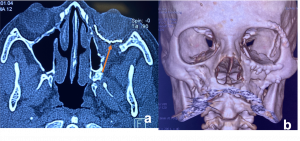

Bone remodelling may be present but no bony erosion. | Pleomorphic Adenoma. a & b). Non-contrast CT scan demonstrates well-defined, round to oval lesions, smooth in outline, associated with prominent scalloped lacrimal fossa (orange curved line) formation due to pressure without bone erosion in comparison to left orbit (orange arrows). Long-standing large tumours lobulations and radiolucent areas of cystic degeneration. |